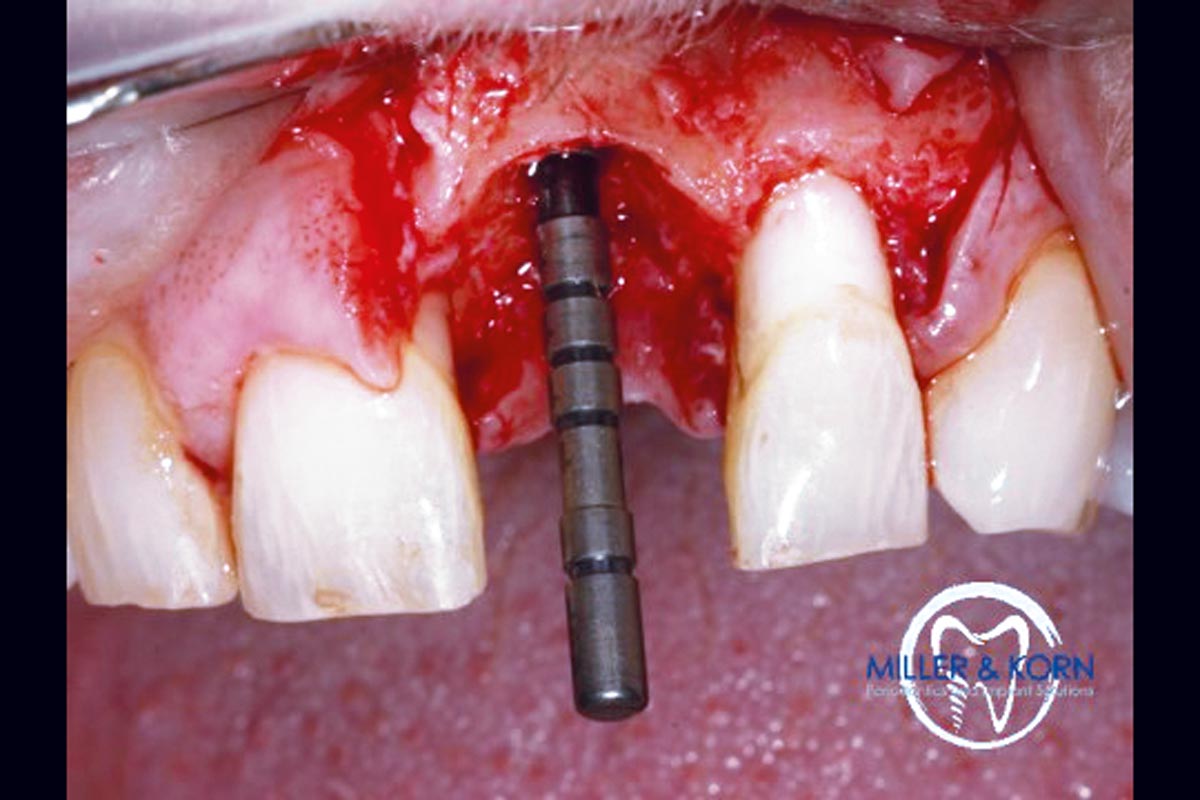

11/39 - Positioning of a direction indicatorImmediate implant placement and correction of horizontal and vertical bone loss using an allograft bone ring, cerabone® and Jason® membrane - Drs. Miller and Korn

12/39 - Positioning of a direction indicatorImmediate implant placement and correction of horizontal and vertical bone loss using an allograft bone ring, cerabone® and Jason® membrane - Drs. Miller and Korn